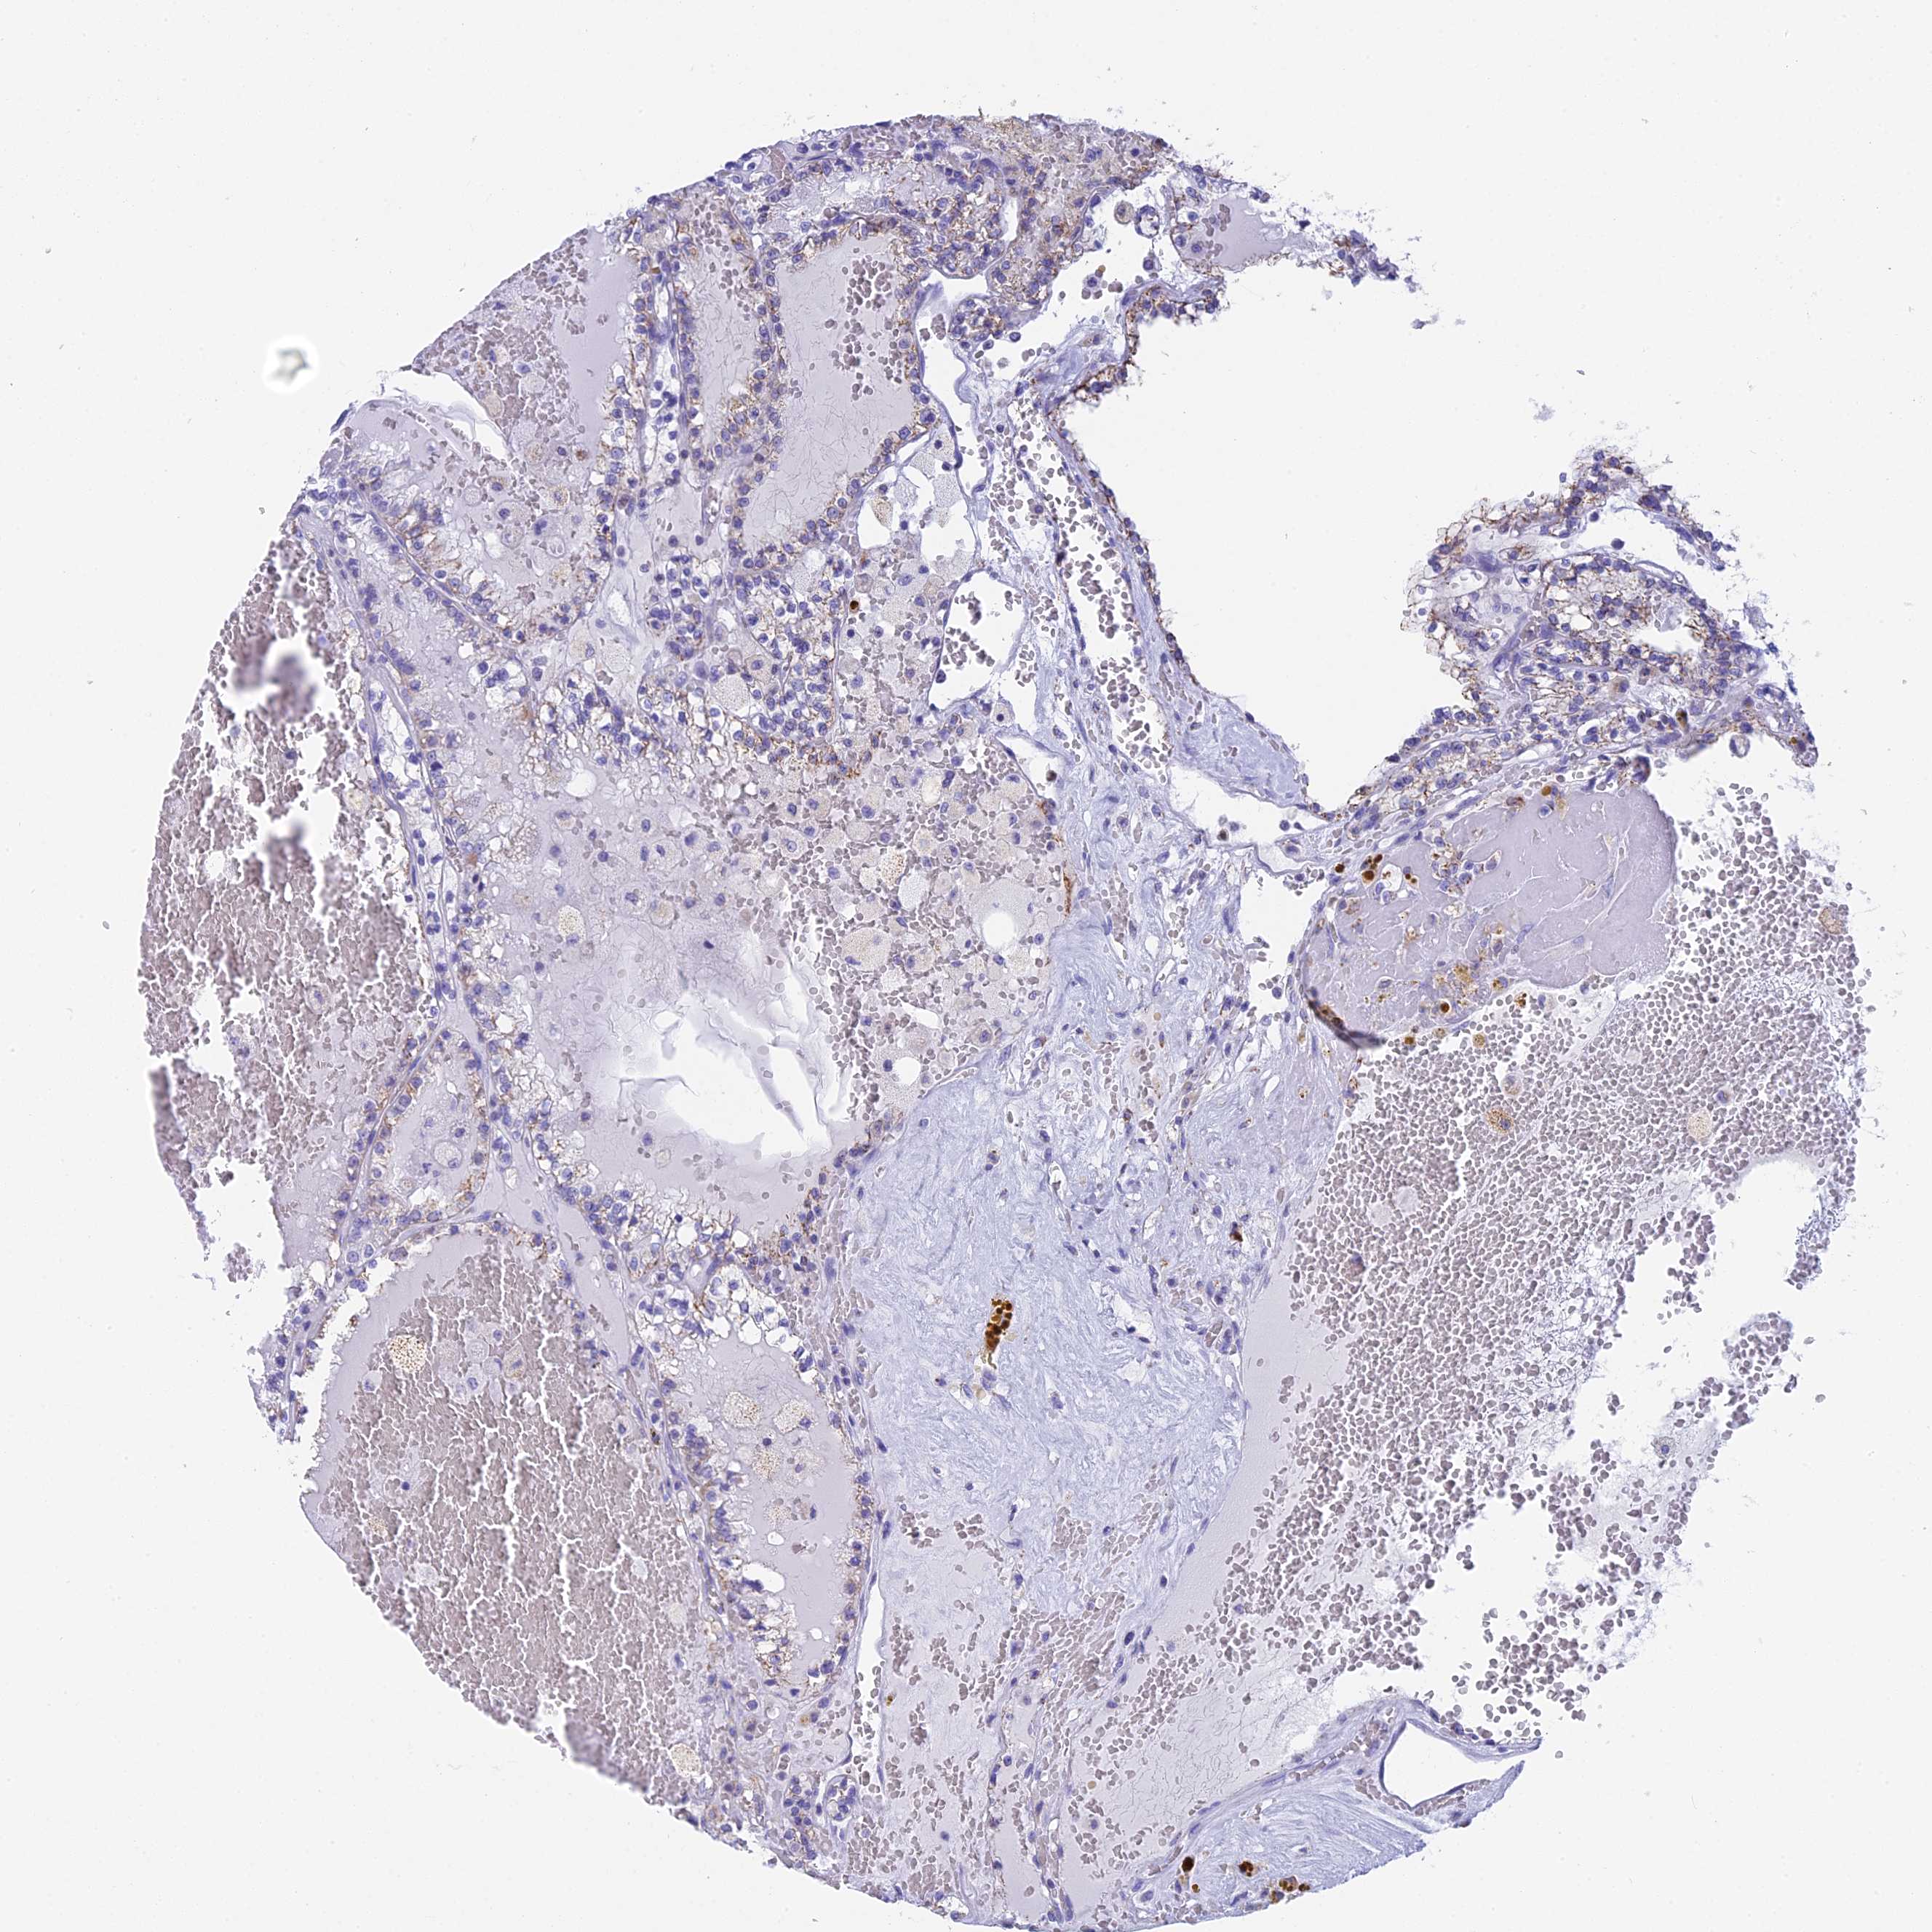

KIDNEY RENAL CLEAR CELL CARCINOMA (VALIDATION) - Interactive survival scatter ploti

The Survival Scatter plot shows the clinical status (i.e. dead or alive) for all individuals in the patient cohort, based on the same data that underlies the corresponding Kaplan-Meier plots. Patients that are alive at last time for follow-up are shown in blue and patients who have died during the study are shown in red.

The x-axis shows the expression levels (FPKM) of the investigated gene in the tumor tissue at the time of diagnosis. The y-axis shows the follow-up time after diagnosis (years). Both axes are complimented with kernel density curves demonstrating the data density over the axes. The top density plot shows the expression levels (FPKM) distribution among dead (red) and alive patients (blue). The right density plot shows the data density of the survived years of dead patients with high and low expression levels respectively, stratified using the cutoff indicated by the vertical dashed line through the Survival Scatter plot. This cutoff is automatically defined based on the FPKM cutoff that minimizes the p-score. The cutoff can be changed by dragging the vertical line or by entering a cutoff value in the square labeled "Current cut-off".

Under the Survival Scatter plot the p-score landscape (black curve; left axis) is shown together with dead median separation (red curve; right axis). Dead median separation is the difference in median mRNA expression between patients who have died with high and low expression, respectively. It is calculated as follows: median FPKM expression of dead patients with high expression - median FPKM expression of dead patients with low expression. This is intended to aid the user in visually exploring custom cutoffs and the associated p-scores and dead median separation.

Individual patient data is displayed and can be filtered by clicking on one or more of the category buttons on the top of the page. Categories describing expression level and patient information include: high, low, alive, dead, female, male and tumor stages. The scale of the x-axis can be toggled between linear and log-scale by clicking on the "x log" button. Mouse-over function shows TCGA ID, patient information and mRNA expression (FPKM) for each patient.

& Survival analysisi

Kaplan-Meier plots summarize results from analysis of correlation between mRNA expression level and patient survival. Patients were divided based on level of expression into one of the two groups "low" (under cut off) or "high" (over cut off). X-axis shows time for survival (years) and y-axis shows the probability of survival, where 1.0 corresponds to 100 percent.

IL17B is not prognostic in Kidney Renal Clear Cell Carcinoma (validation)